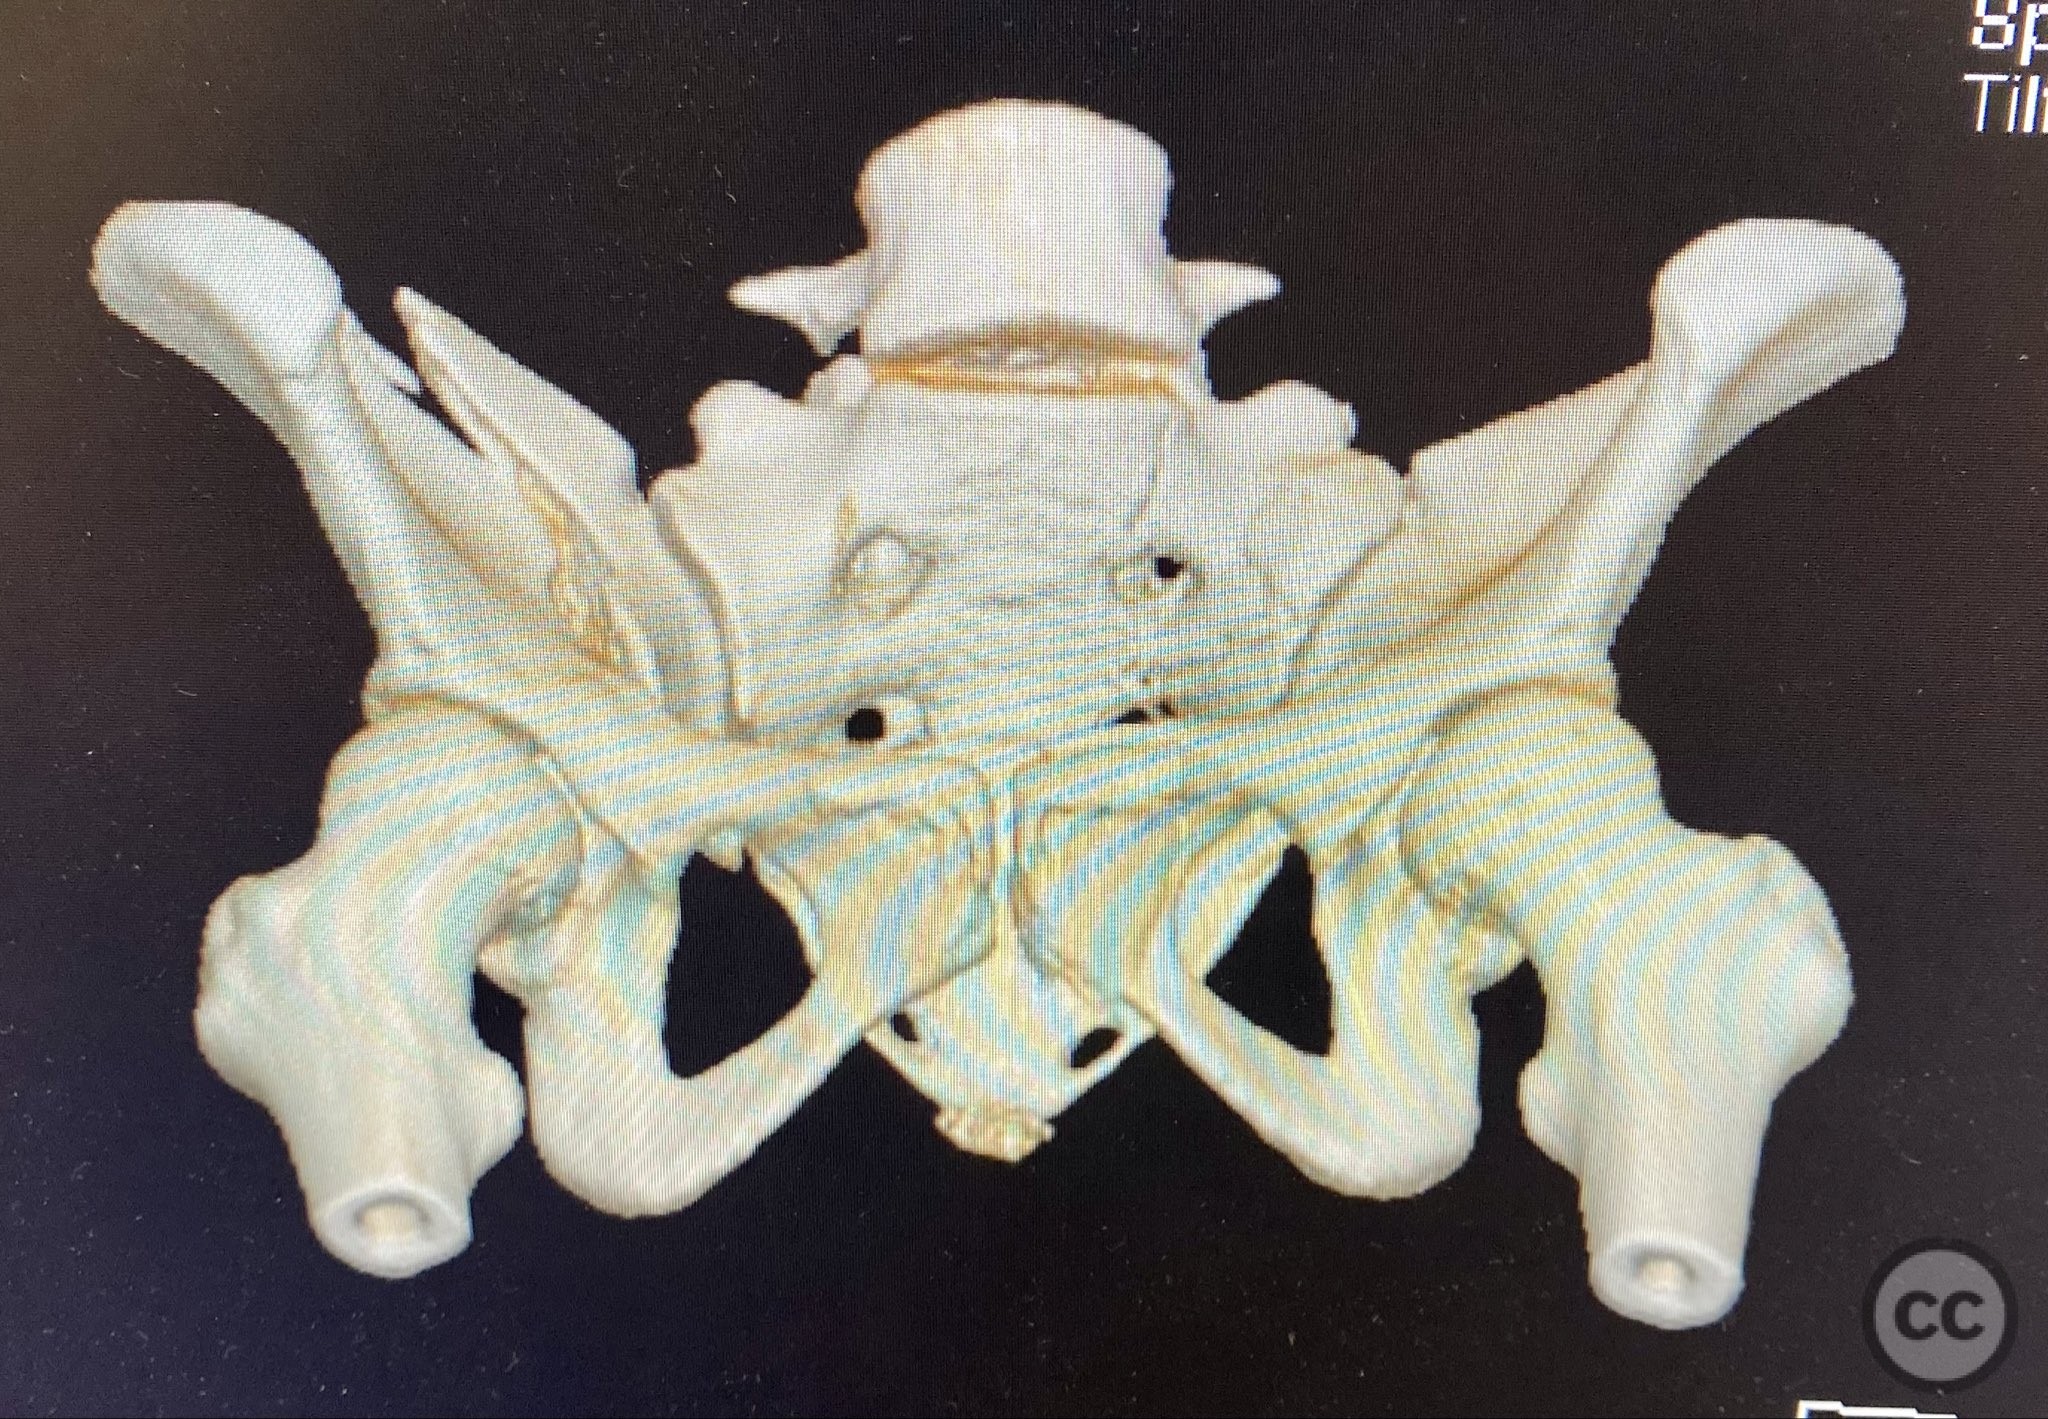

Clinical Details

Clinical and radiological findings:  The patient presented following trauma with an unusual, significantly displaced right iliac fracture, accompanied by left-sided sacral and parasymphyseal ramus fractures. Initial AP pelvic radiography demonstrated the complex injury pattern. CT imaging provided detailed characterization of the iliac and sacral fractures, including assessment of displacement, bone quality, soft tissue status, and overall body habitus. No neurovascular compromise was reported. AO/OTA classification: Right iliac fracture 61B2.3 (partial unstable, lateral compression injury), left sacral fracture Denis zone I, left parasymphyseal ramus fracture.

Planning remarks:  The preoperative plan included initial application of bilateral distal femoral traction to achieve provisional reduction, particularly targeting the sacral displacement. Definitive surgical management consisted of percutaneous stabilization of the left sacral fracture and open reduction with internal fixation (ORIF) of the right iliac fracture via an anterior approach, with planned placement of pelvic brim cancellous screws.